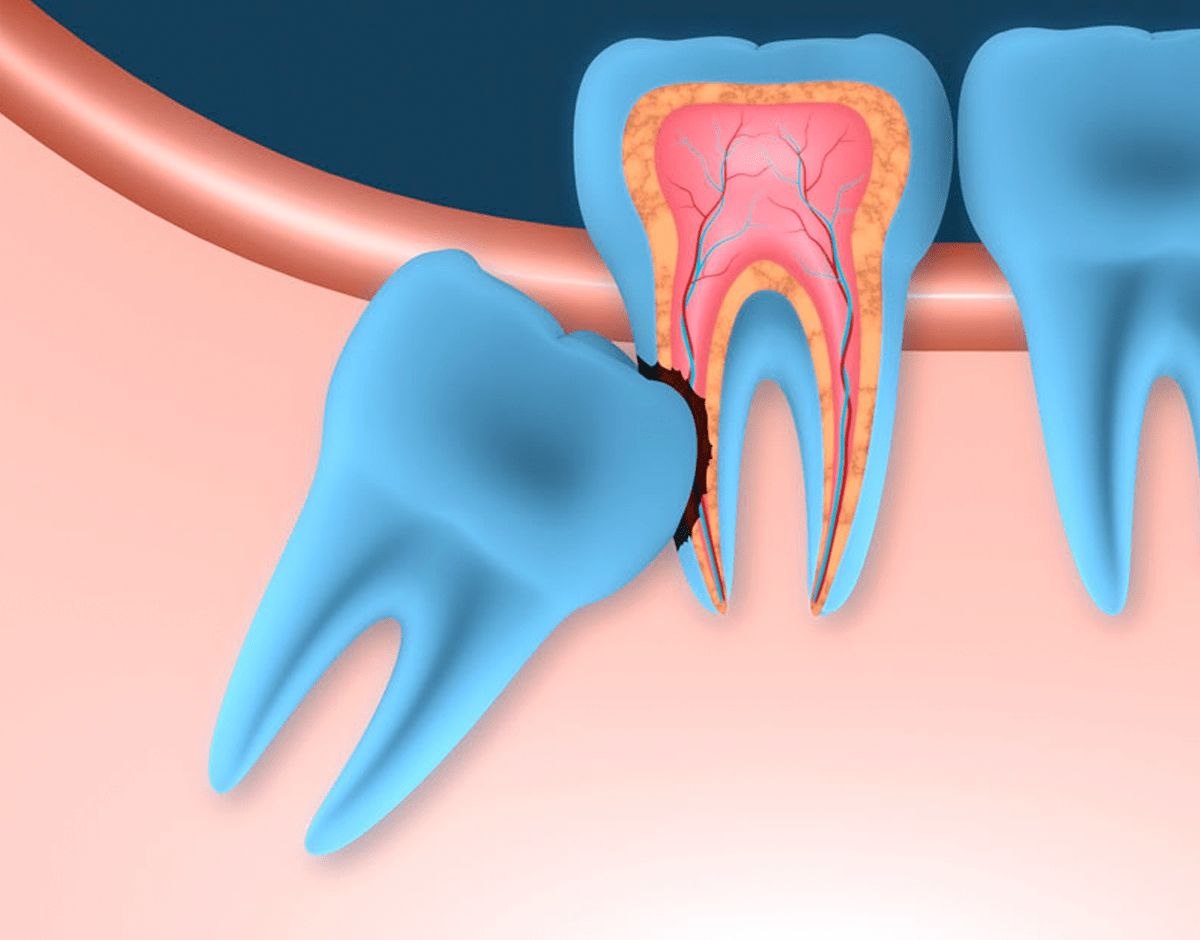

1. Рассасывание корня седьмого зуба

Да, это возможно, но встречается примерно в 4,78% случаев — то есть довольно редко.

От чего зависит риск

Ключевой фактор — наклон восьмого зуба.

👉 Чем сильнее зуб наклонён — тем выше риск проблем

👉 Чем положение более ровное — тем риск ниже

Чем больше зуб покрыт костной тканью и не имеет сообщения с полость рта, как в позициях V3/M3; H3/B3; A1, кариес на нём не развивается.

При положении В2/М2; Н2/V2 риск уже значительно выше, из-за частичного прорезывания и наличия сообщения с полостью рта.